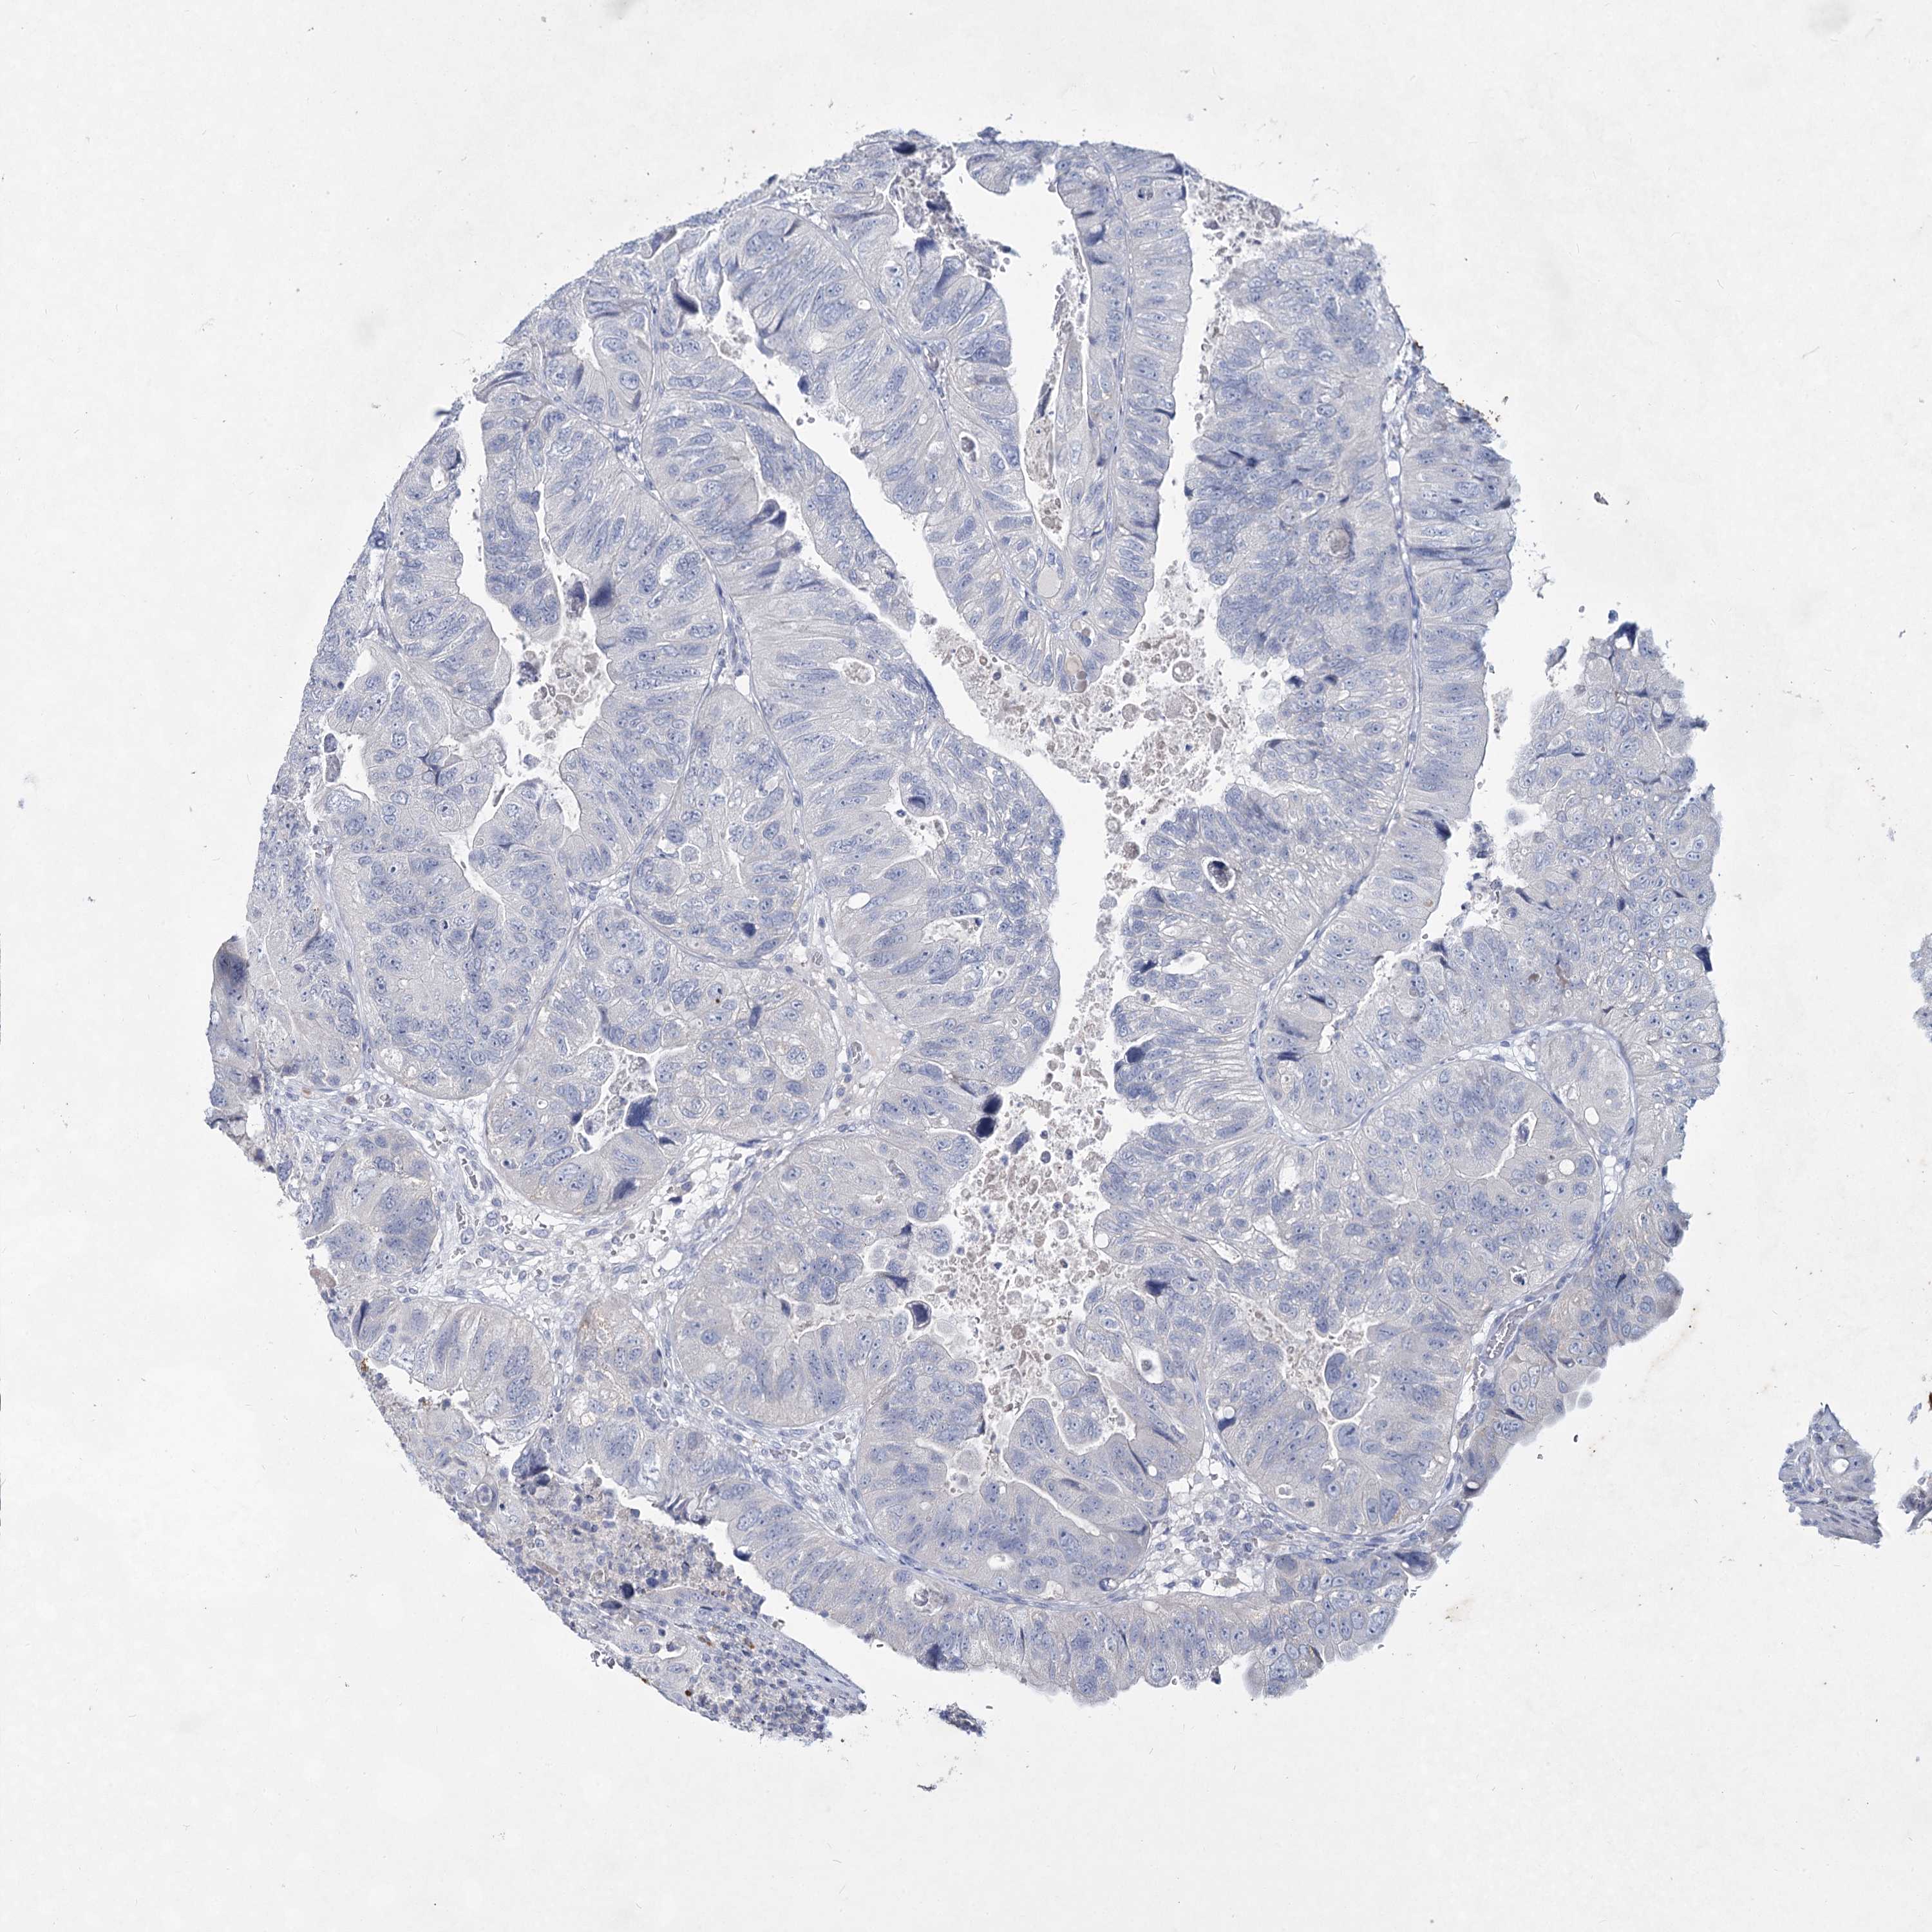

CANCER COLORECTAL CANCER Show tissue menu

Colorectal cancer

Human cancer

Colon adenocarcinoma

Rectum adenocarcinoma